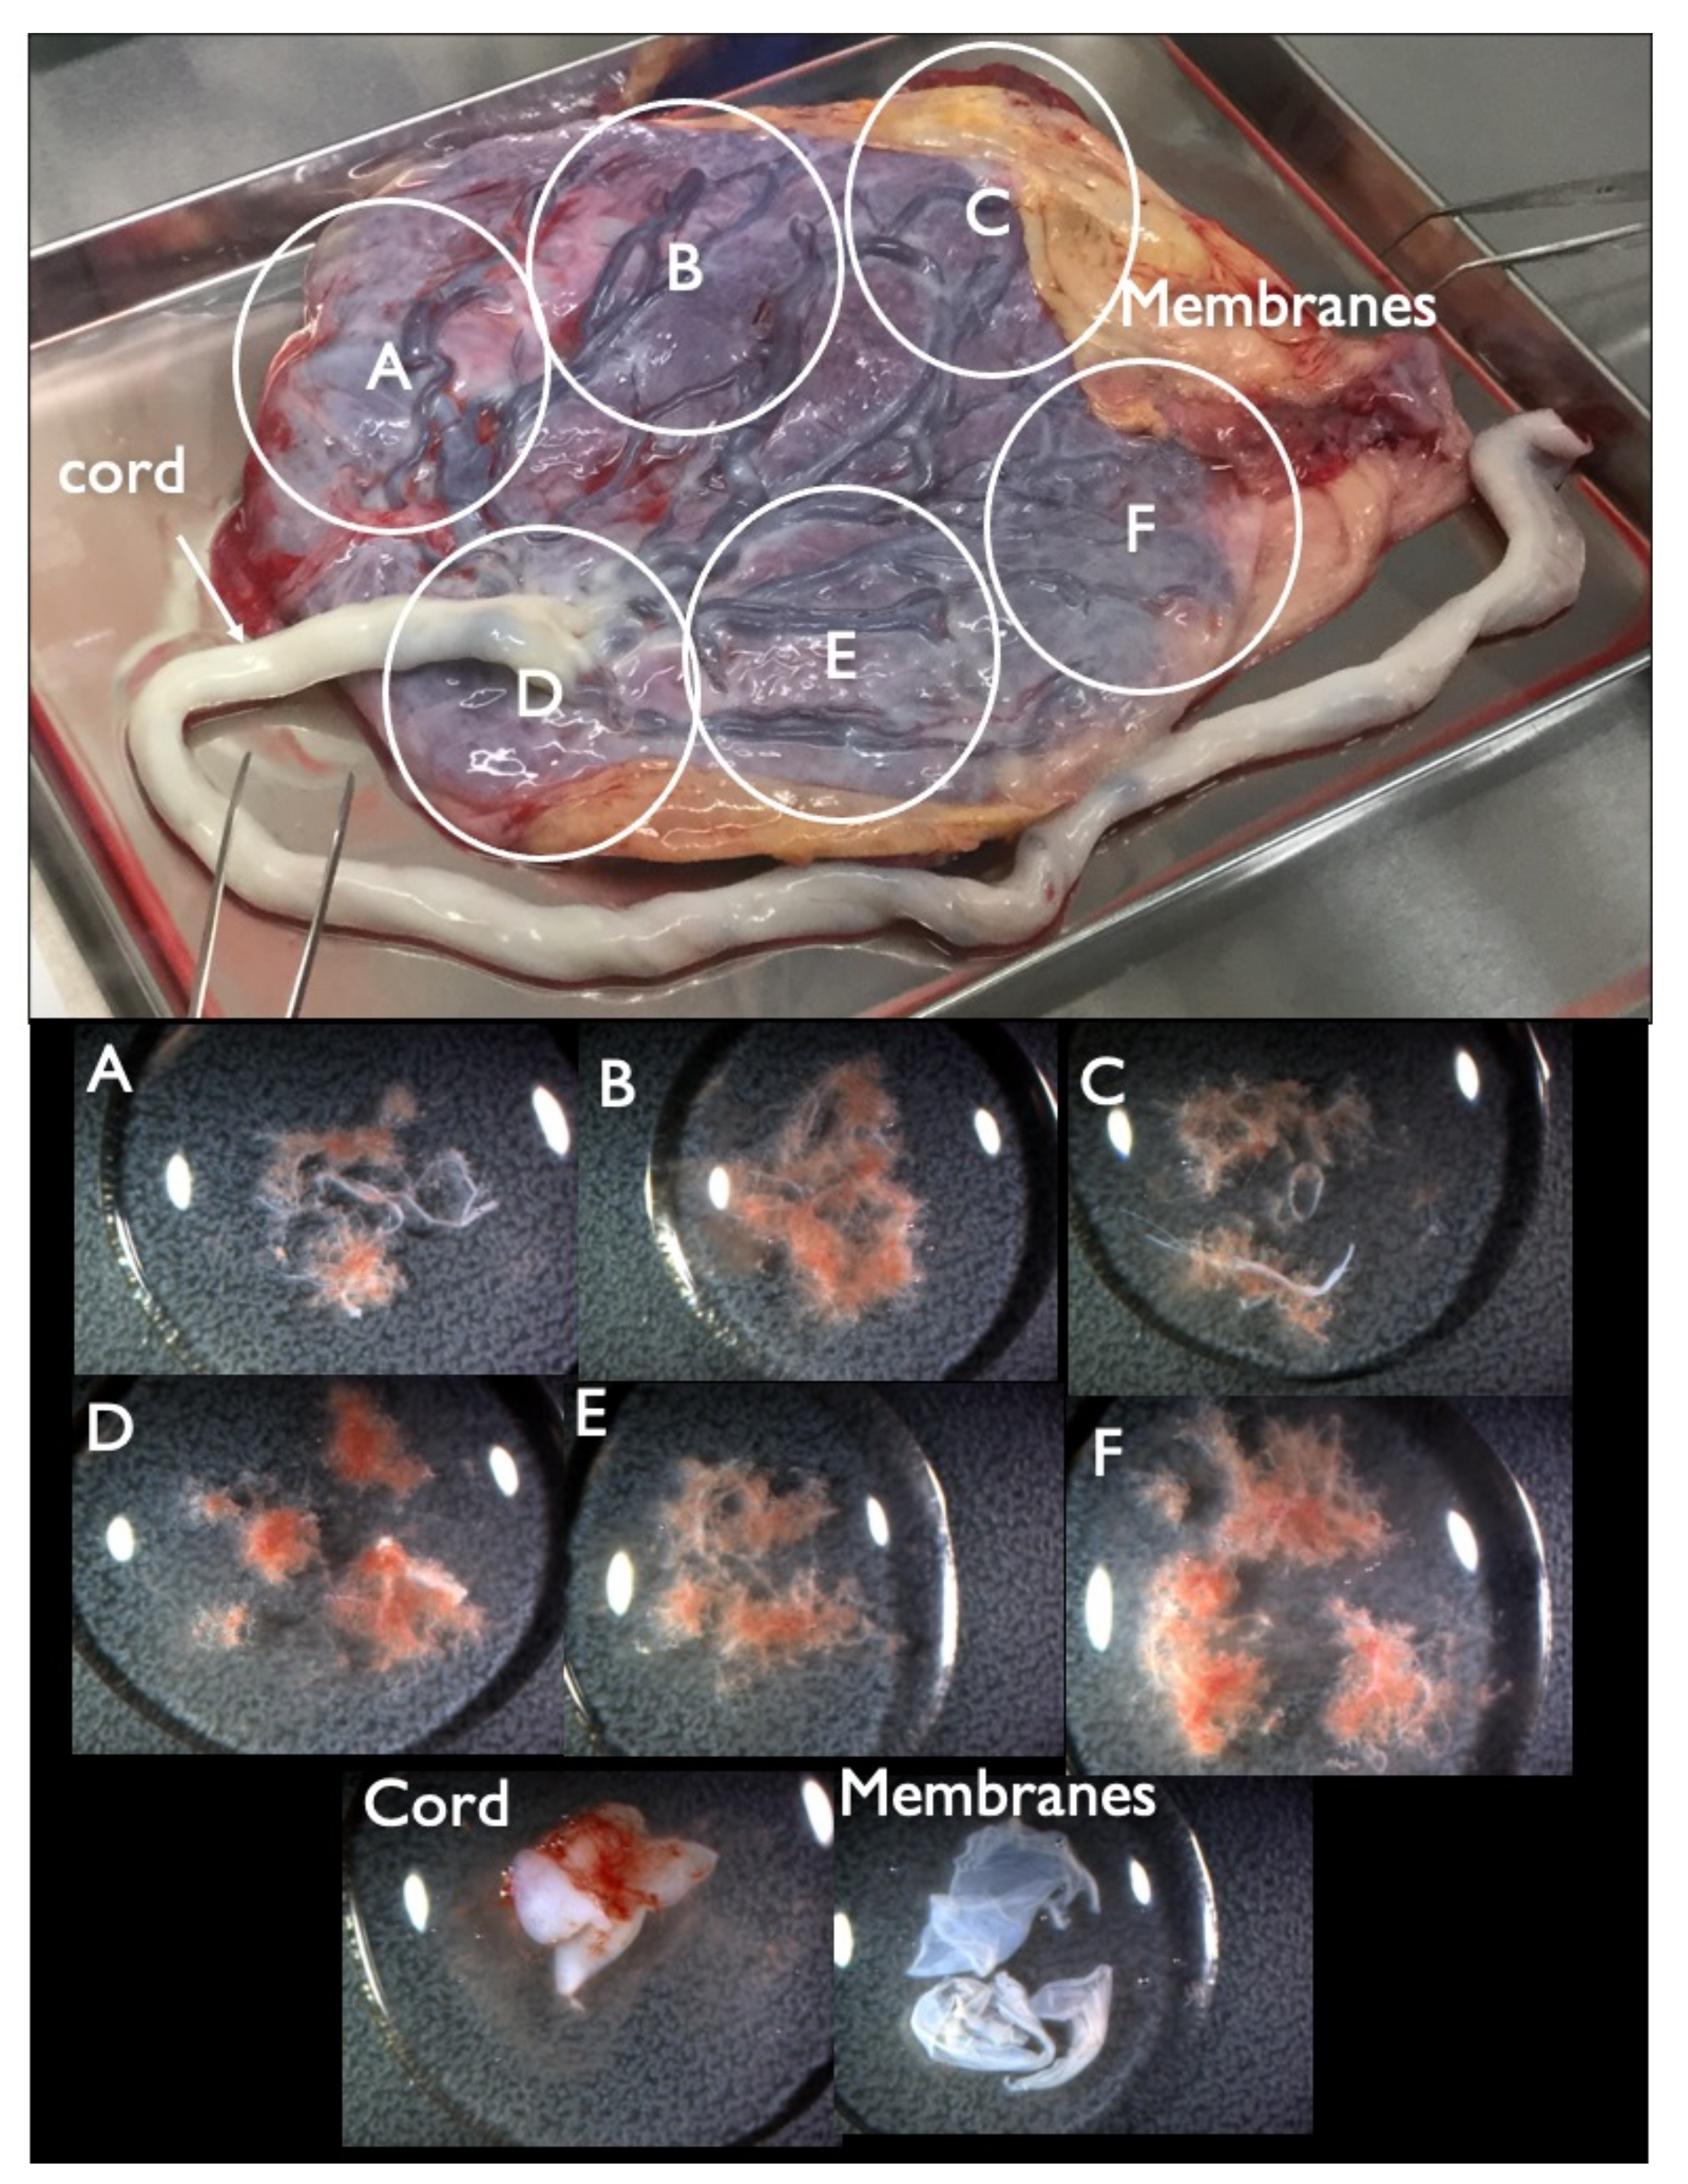

| Case | CVS G–Band | CRITO Result | CRITO Z–Score | Placental Part | Cord | Membranes | Maternal Blood | Causal Factor of FP/FN Result | Increased NT | NT (mm) | Sonographic Findings | |||||

|---|---|---|---|---|---|---|---|---|---|---|---|---|---|---|---|---|

| A | B | C | D | E | F | |||||||||||

| FP1 | 45,X | T21 positive | 3.55 | MX+ T21 (16%) | MX+D21 | MX+ T21 (8%) | MX+D21 | – | – | MX+ T21 (4%) | 46,XX | CPM | + | 8.8 | Increased NT, CH, General edema, PE bilateral, Small NB, Tachycardia, Short FL/HL, Turner is strongly suspected | |

| FP2 | 46,XX | T21 positive | 4.18 | D21 | D21 | D21 | D21 | D21 | D21 | D21 | D21 | 46,XX | s/o nonviable twin with T21 | – | 2.2 | TR mild, DCDA vanishing twin with a nonviable fetus |

| FP3 | 46,XY | T21 positive | 7.52 | D21 | D21 | D21 | D21 | D21 | D21 | D21 | T21 (14–74%) * | 46,XX | nonviable twin with T21 | – | 1.4 | Small NB, TR mild, DCDA vanishing twin with a nonviable fetus |

| FP4 | 46,XY | T21 positive | 7.78 | D21 | D21 | D21 | D21 | T21 (15%) | D21 | D21 | D21 | 46,XX | CPM | – | 2.2 | Small NB, TR mild |

| FP5 | 46,XX | T18 positive | 4.20 | D18 | D18 | D18 | D18 | D18 | D18 | D18 | D18 | 46,XX | unclear | – | 2.1 | TR mild, DV reverse |

| FP6 | 46,XX | T18 positive | 12.76 | D18 | D18 | D18 | D18 | D18 | D18 | D18 | D18 | 46,XX | unclear | – | 2.2 | TR mild–moderate |

| FP7 | 46,XY | T18 positive | 5.49 | D18 | D18 | D18 | D18 | – | – | D18 | D18 | 46,XX | unclear | – | 1.6 | TR mild |

| FP8 | 46,XY | T18 positive | 3.56 | D18 | D18 | D18 | D18 | D18 | D18 | D18 | D18 | 46,XX | unclear | – | 2.0 | TR mild, SFD, SCH |

| FP9 | 46,XX | T18 positive | 3.22 | D18 | D18 | D18 | D18 | D18 | D18 | D18 | D18 | 46,XX | unclear | – | 1.2 | no particular findings |

| FP10 | 46,XX | T18 positive | 3.02 | – | – | – | – | – | – | – | – | 46,XX | unclear | – | 1.8 | TR mild |

| FN1 | 47,XY,+21 | T21 negative | 1.07 | – | – | – | – | – | – | – | – | 46,XX | unclear | + | 7.2 | Increased NT, GE mild, NB defect, Lowset ear, TR mild, Small stomach, DV reverse, Tachycardia, T21 is strongly suspected |

| Case FP3–Specimen | FISH | G–Band | |

|---|---|---|---|

| Disomy 21 | Trisomy 21 | ||

| Placenta–A | 100% | 0% | 46,XY |

| Placenta–B | 100% | 0% | culture failure |

| Placenta–C | 100% | 0% | 46,XY |

| Placenta–D | 100% | 0% | 46,XY |

| Placenta–E | 100% | 0% | 46,XY |

| Cord | 100% | 0% | 46,XY |

| Membranes–1 | 86% | 14% | – |

| Membranes–2 | 90% | 10% | – |

| Membranes–3 | 16% | 74% | 47,XY,+21 |

| Membranes–4 | 100% | 0% | – |

| Membranes–5 | 100% | 0% | – |